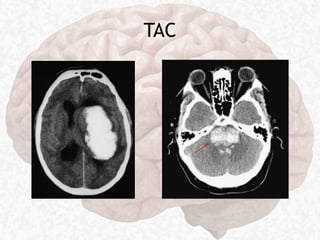

TAC